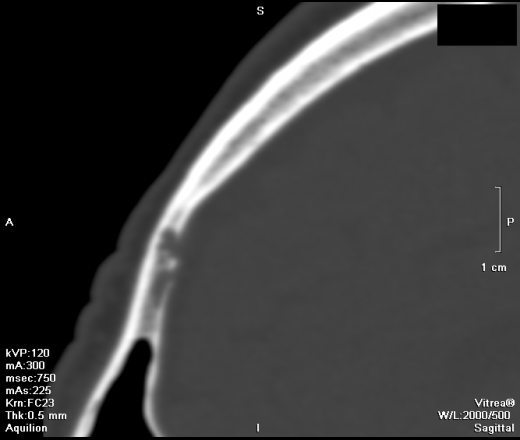

- https://radiomed.ru/sites/default/files/styles/case_slider_image/public/user/5821/1303118895.593.png?itok=Eic1AKYB

- https://radiomed.ru/sites/default/files/styles/case_slider_image/public/user/5821/1303118902.156.png?itok=pHc7od_7

- https://radiomed.ru/sites/default/files/styles/case_slider_image/public/user/5821/1303118910.250.png?itok=et1QTGXF

- https://radiomed.ru/sites/default/files/styles/case_slider_image/public/user/5821/1303118921.187.png?itok=SnhkGwSh

- https://radiomed.ru/sites/default/files/styles/case_slider_image/public/user/5821/1303118924.187.png?itok=_hTxi0xR

- https://radiomed.ru/sites/default/files/styles/case_slider_image/public/user/5821/1303118926.828.png?itok=V5geQffw

- https://radiomed.ru/sites/default/files/styles/case_slider_image/public/user/5821/1303118934.001.png?itok=lgI5vH_Y

Первая мысль была о гистиоцитозе Х. Клиника, цель исследования? Случайная ли находка?

Попробуйте посмотреть с разной толщиной среза, можно в MIP. Возможно это расширенные диплоические вены. Дефекты не на всю толщину кости, похоже только в диплоэ.

цель исследования ОНМК? на КТ дисциркуляторные очаги, ничего свежего. Находка случайная

Вены.